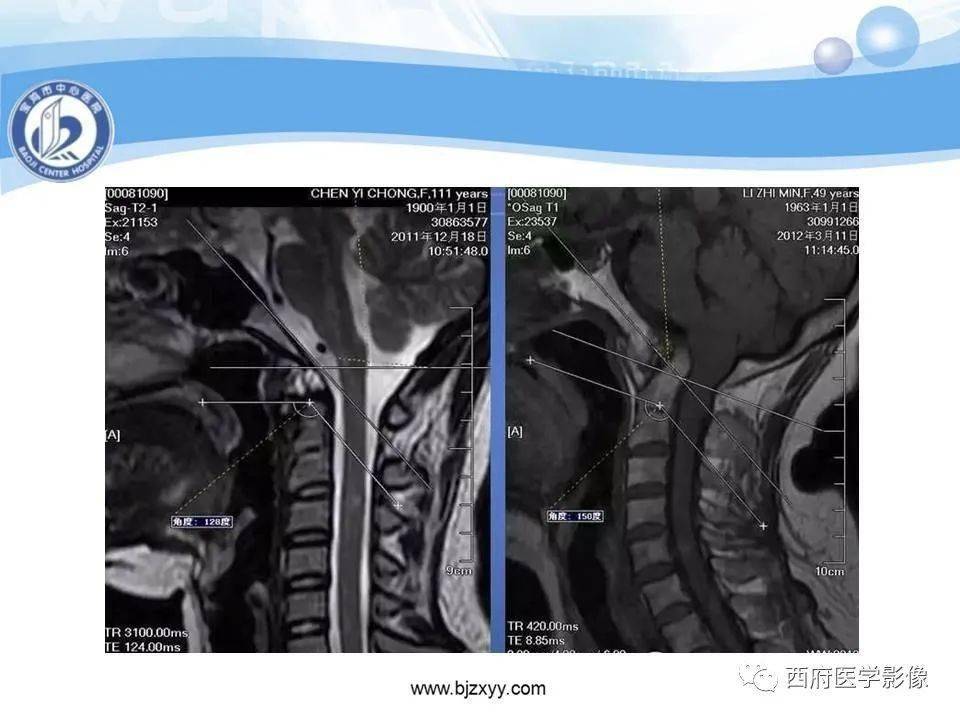

颅底凹陷症影像学诊断

颅底凹陷症的影像诊断与鉴别诊断